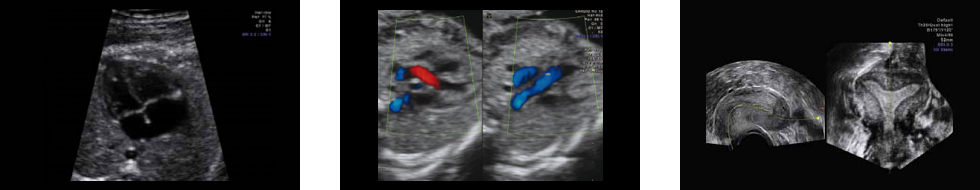

Режим двух изображений. Выходные тракты правого и левого желудочков.

Технология HD-Flow